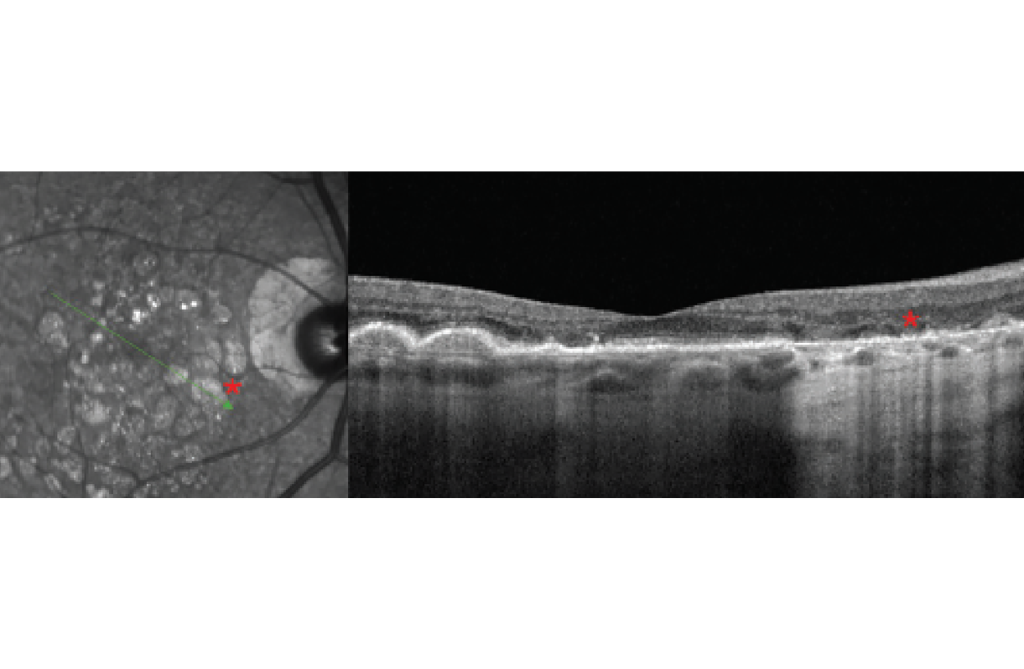

FIGURA 6

Las imágenes infrarrojas son un recurso valioso que puede ayudar a interpretar otras modalidades de imagen como OCT y FAF y a menudo pueden detectar enfermedad macular sutil como drusas tempranas o depósitos drusenoides subretinianos (anteriormente pseudodrusas reticulares), que pueden ser visibles en imágenes infrarrojas pero no clínicamente evidentes. Los informes de CAM también destacaron el uso de imágenes infrarrojas en DMAE para detectar GA ( Figura 6 ). Los hallazgos infrarrojos de GA se definieron como lesiones altamente reflectantes mayores de 250 µm con bordes bien definidos. 10 Mientras que las lesiones de GA son hipo-FA con FA de longitud de onda corta, aparecen tan brillantemente reflectantes con nIR ya que las longitudes de onda infrarrojas son fuertemente reflejadas por la esclerótica. Las longitudes de onda infrarrojas también tienen uso para resaltar lesiones maculares inflamatorias como las que se observan en la neurorretinopatía macular aguda, que aparecen como lesiones petaloides oscuras correspondientes a áreas de interrupción de la zona elipsoide observadas en OCT, pero pueden no ser clínicamente evidentes ( Figura 7 ). Estas imágenes también son útiles para detectar complejos neovasculares sutiles en la retinopatía diabética proliferativa que son difíciles de visualizar clínicamente sin angiografía con fluoresceína.